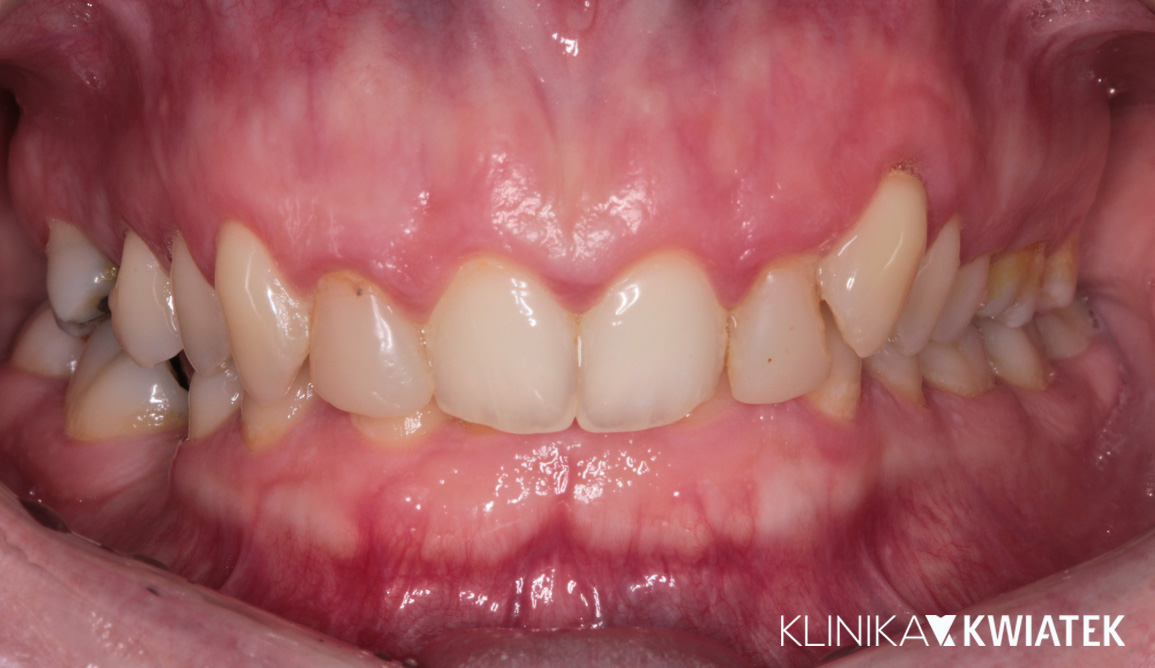

Kompleksowe leczenie i odbudowa funkcji – droga do pięknego uśmiechu

Do naszej Kliniki zgłosił się Pacjent z poważnymi problemami stomatologicznymi – licznymi ubytkami, nieprawidłowym zgryzem oraz widocznym starciem zębów, co wpływało na estetykę i funkcję. Przeprowadziliśmy kompleksowy plan leczenia: od diagnostyki, higienizacji i leczenia zachowawczego, przez szynoterapię i leczenie implantologiczne, aż po pełną odbudowę protetyczną. Efekt końcowy to zdrowy, harmonijny uśmiech oraz pełny komfort w codziennym funkcjonowaniu.